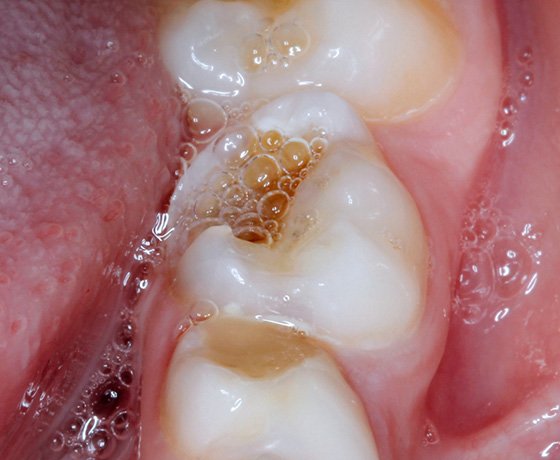

Occlusal view of the carious lesion tooth. A medium excavator was used to determine the depth of the affected (darker) dentin under the infected dentin.